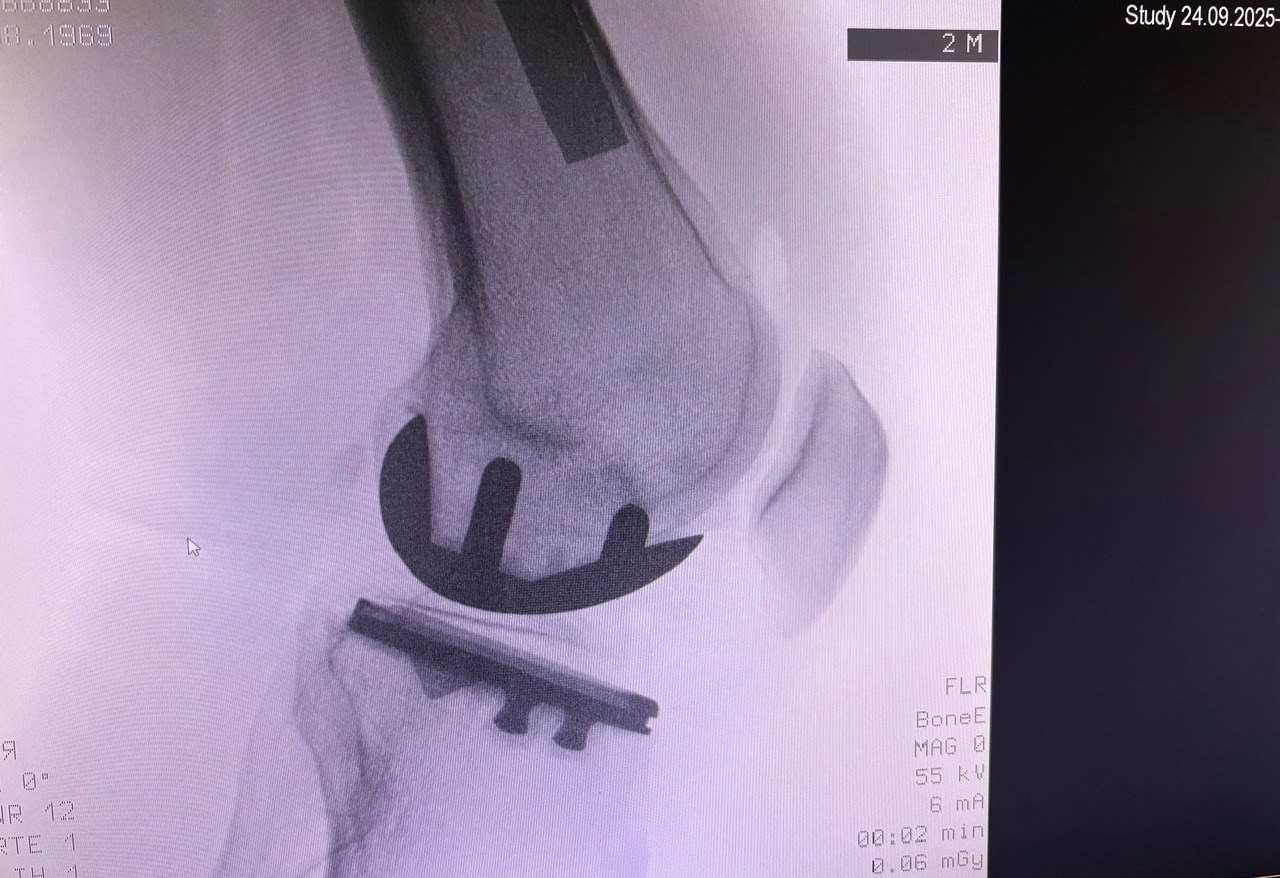

Η ημιολική αρθροπλαστική γόνατος (partial / unicompartmental knee replacement) είναι επέμβαση όπου αντικαθίσταται μόνο το φθαρμένο διαμέρισμα του γόνατος και όχι ολόκληρη η άρθρωση.

Πώς γίνεται

- Μικρότερη τομή από την ολική

- Αντικατάσταση μόνο του πάσχοντος διαμερίσματος

- Διάρκεια επέμβασης: ~1 ώρα

Η τελική επιλογή της χειρουργικής τεχνικής γίνεται μετά από αναλυτική κλινική αξιολόγηση και προσεκτικό προεγχειρητικό σχεδιασμό, με στόχο το βέλτιστο και ασφαλέστερο αποτέλεσμα για τον ασθενή. Απαραίτητη προϋπόθεση για την επίτευξη εξαιρετικών αποτελεσμάτων αποτελεί η εξειδίκευση του χειρουργού στη συγκεκριμένη τεχνική, καθώς και η εκτεταμένη εμπειρία με μεγάλο αριθμό επεμβάσεων. Ο έμπειρος ορθοπαιδικός Νικόλαος Καλύβας εφαρμόζει την Ημιολική αρθροπλαστική γόνατος (Μονοδιαμερισματική) επί σειρά ετών στη Γερμανία, έχοντας χειρουργήσει μεγάλο αριθμό ασθενών. Τα τελευταία χρόνια, από τη θέση του Αναπληρωτή Διευθυντή σε ένα από τα μεγαλύτερα κέντρα αρθροπλαστικής της Γερμανίας, είχε ενεργό ρόλο στην εκπαίδευση ειδικευομένων ορθοπαιδικών στη συγκεκριμένη τεχνική.